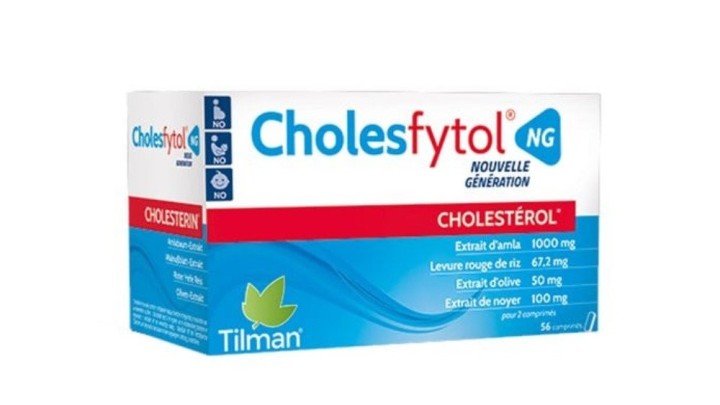

Vitamins & Supplements